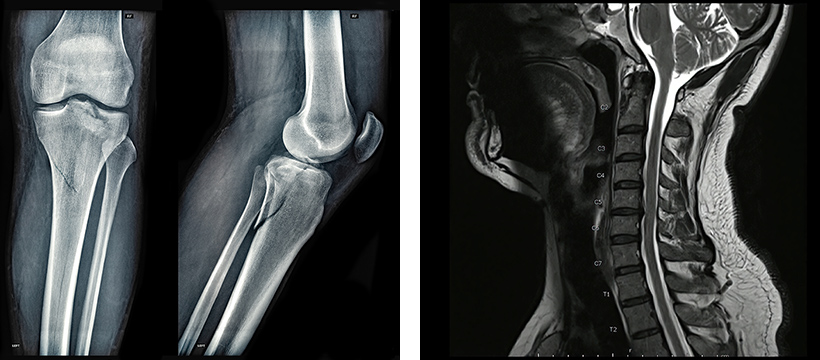

必要に応じてMRI検査を予約。現在の状態を正確に把握します。

ヒアルロン酸注射で効果がなく、人工関節を勧められていた方。幹細胞5,000万個の投与3ヶ月後に痛みが大幅改善。

人工関節を勧められていた方。1億個を2回投与し、最終投与後1年で痛み完全消失。日常生活を取り戻されました。

関節鏡手術を勧められていた方。5,000万個を3回投与し、半年後に痛み消失。ゴルフ講師の仕事にも復帰されました。

脳出血(右視床出血)による左半身麻痺。発症2週間後に2億個を3回投与。握力が2.4倍に回復し、杖なし歩行が可能に。

頚椎症性脊髄症の術後も症状が残存。脊髄腔内に2,500万個を3回投与。歩行距離が約17倍に改善し、膀胱直腸障害も改善。